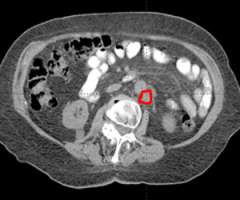

The second row shows images (axial, coronal, and sagittal) of the distribution of the radiation dose that was delivered to this area. One can see that the dose of radiation to this target is very tightly distributed to avoid as much normal tissue as possible.